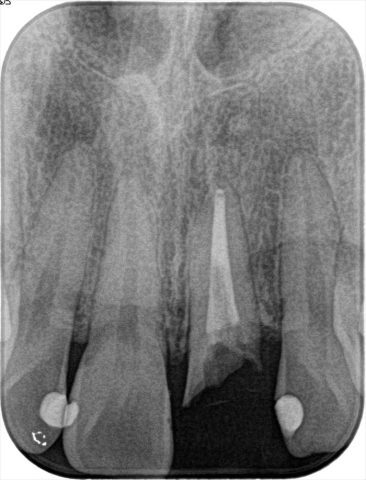

初診時のデンタルレントゲン写真です。

歯冠部分がむし歯になることによって朽ちて消えかかっています。